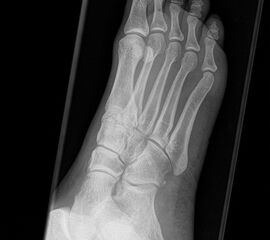

Fuß dp (dorsoplantar) mit Belastung

Positionierung:

• Der Patient steht unter gleichmäßiger Gewichtsbelastung auf beiden Füßen.

• Die Fußachse ist nach vorne gerichtet.

• Die Kassette liegt unter dem zu röntgenden Fuß.

• Der Zentralstrahl wird auf das Tarsometatarsalgelenk II zentriert.

• Die Röntgenröhre ist 15° vertikal gekippt.

• Anmerkung: Technisch lässt sich die Röhre beim stehenden Patienten nicht in 0° über dem Fuß positionieren. Eine Kippung der Röhre um 15° erlaubt darüber hinaus eine bessere Einsicht in die tarsometatarsalen Gelenke.

Kennzeichen des Röntgenbildes:

• Standardabbildung des Fußes zusammen mit der belasteten seitlichen Aufnahme und der unbelasteten Schrägaufnahme.

• Die belasteten Aufnahmen liefern relevante Informationen zur Fußstatik und sind die Grundlage aller achskorrigierenden Eingriffe an Vor- und Rückfuß.

• Sämtliche Winkelbestimmungen beziehen sich auf belastete Aufnahmen.

Besondere Bemerkungen zum Beispielbild:

• Schwere Hallux valgus Deformität.

• Die Sesambeine sind luxiert, ebenso das Großzehengrundgelenk. Luxation des Metatarsophalangealgelenks II.

• Degenerative Veränderungen der tarsometatarsalen (TMT) Gelenkreihe, betont TMT II und III.